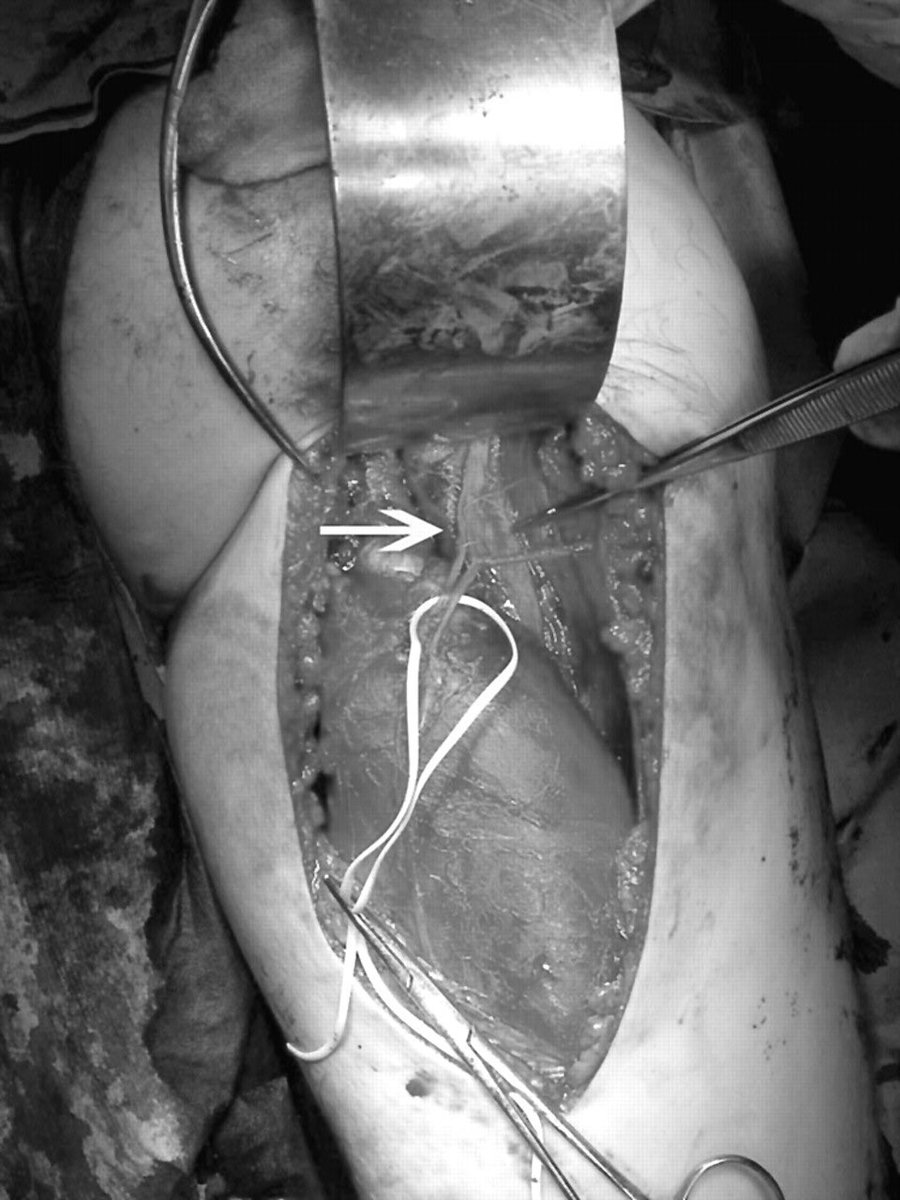

متى قد يحتاج المصاب لإجراء عملية؟

- قطع كامل في العضلة وفقدان وظيفتها.

- قطع كامل في وتر العضلة.

- لو تأثرت المنطقة المحيطة بالعضلة مثل: الاعصاب.

- تكرار الاصابة وتليف العضلة.

- التهاب مزمن في وتر العضلة.